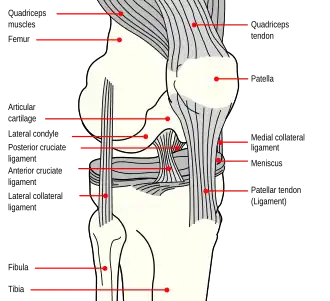

The rectus femoris arises from the anterior inferior iliac spine and from the superior edge of the acetabulum.[1] It is thus a biarticular muscle. The other parts of the quadriceps arise from the surface of the femur. All four parts of the quadriceps muscle ultimately insert into the tuberosity of the tibia via the patella, where the quadriceps tendon becomes the patellar tendon.[1]

-

The quadriceps tendon connects to the top part of the kneecap (patella)

The quadriceps tendon connects to the top part of the kneecap (patella) -